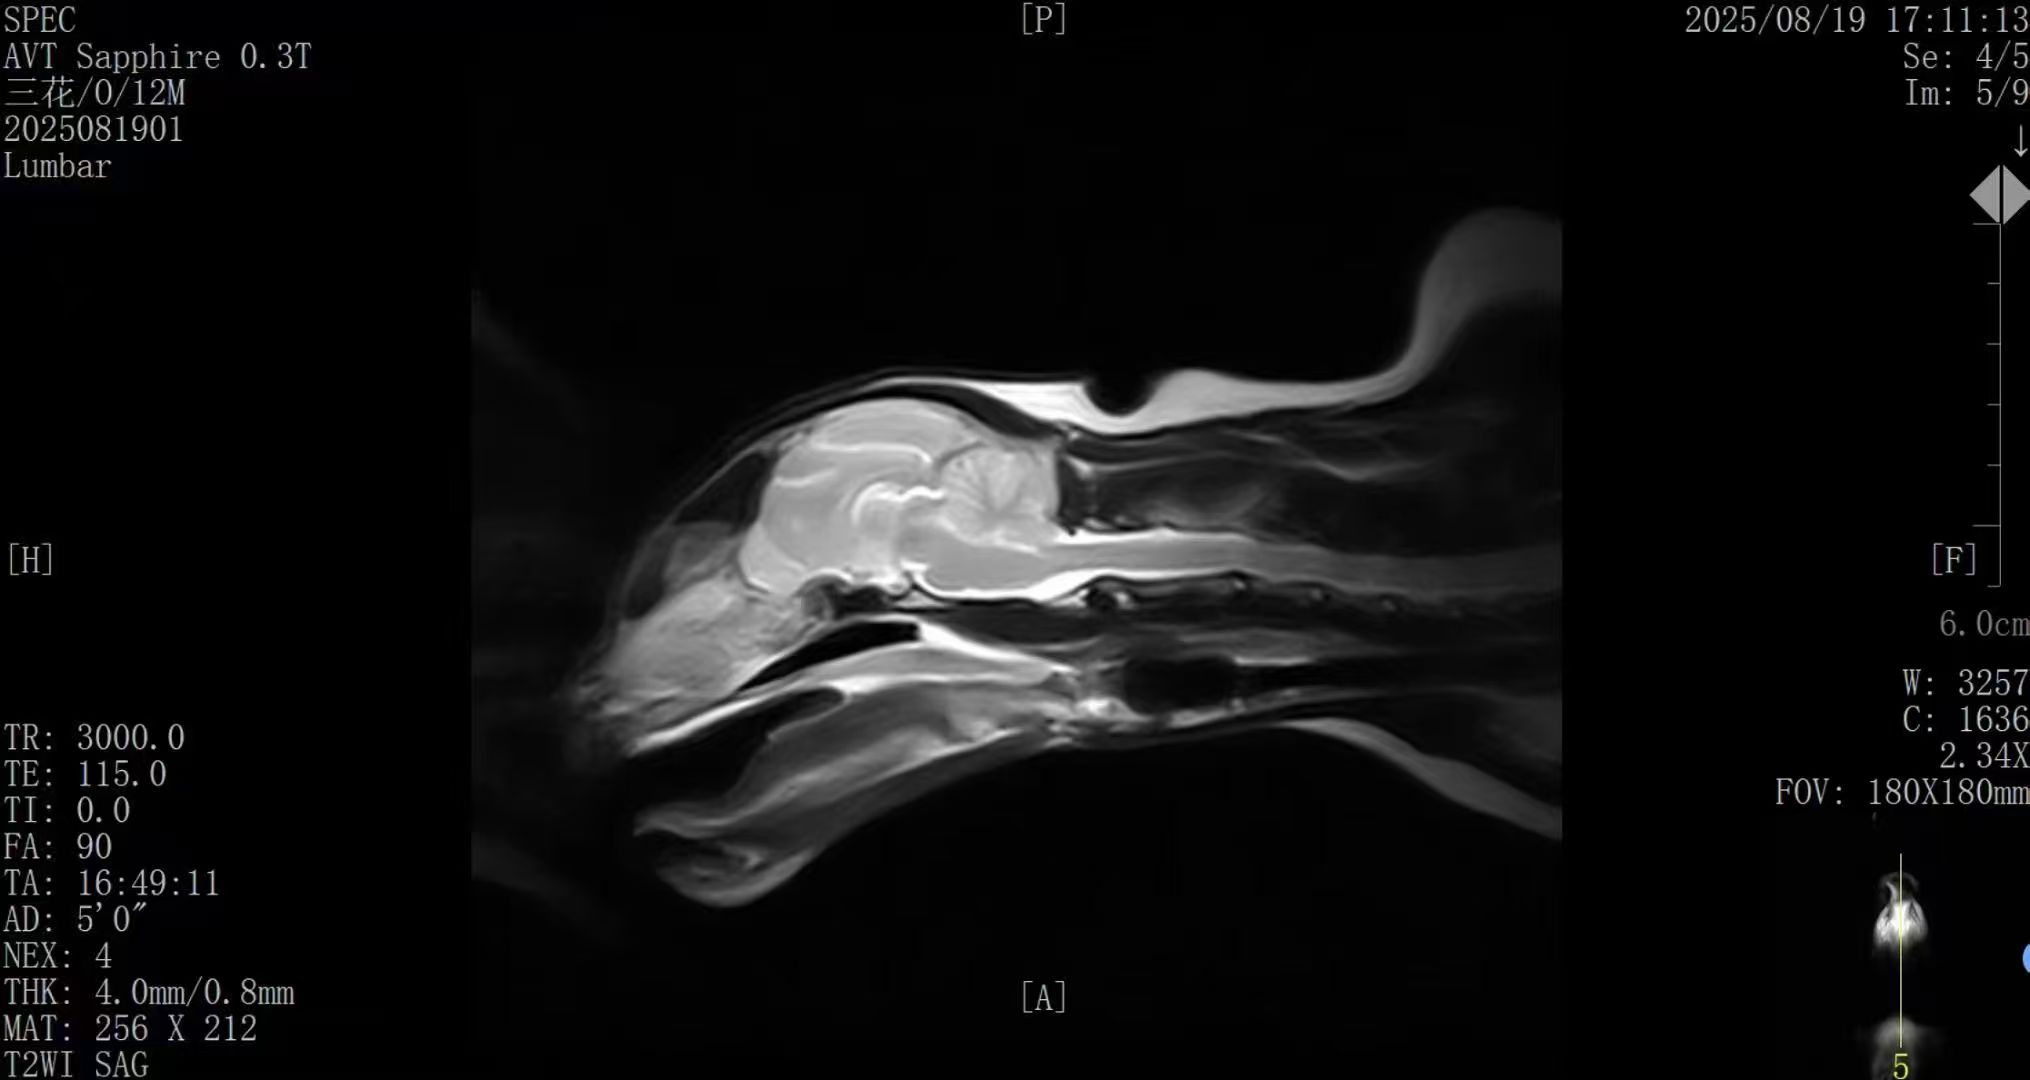

✅ AI智能成像 · 诊断更精准

搭载新一代AI影像优化系统,图像信噪比与组织对比度 整体提升约50%;

在神经、脊柱、关节及软组织等常见病例中表现优异,图像清晰、细节丰富,满足临床精准诊断需求。